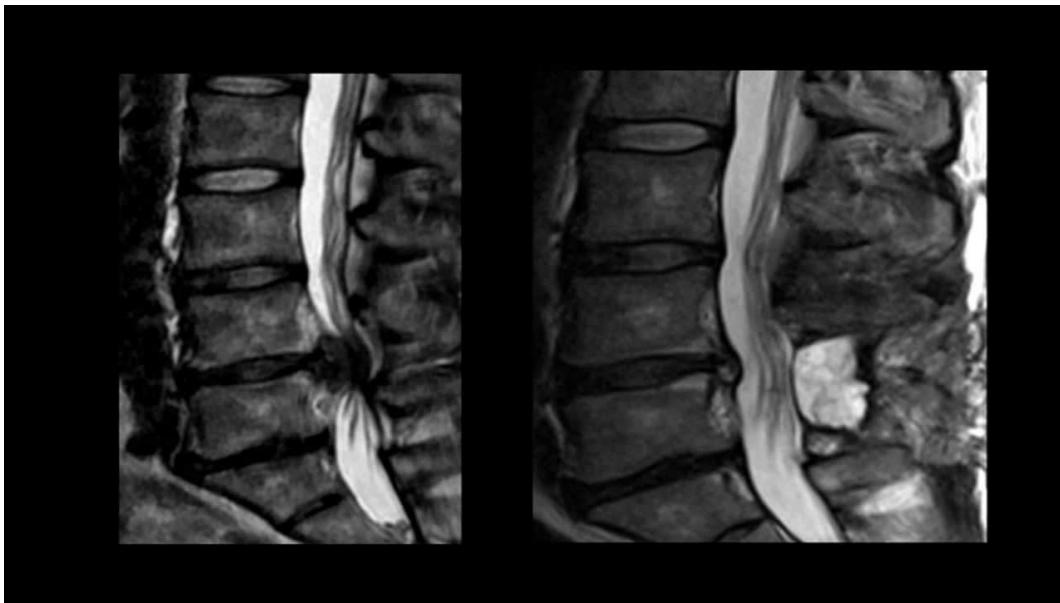

Lumbar Disc Herniation

- Significance: Very common cause of low back pain and unilateral leg pain (radiculopathy)

- Diagnosis: Made clinically and confirmed with MRI studies of lumbar spine

- Initial treatment: Nonoperative with oral medications and physical therapy for radicular leg pain

- Surgical indication: Microdiscectomy for severe pain and/or motor deficit that have failed to respond to nonoperative management

L5/S1 Disc Herniation Example: